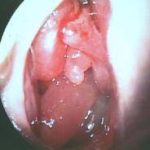

✔ Sialoendoskopi: Küçük kamera ile doğrudan kanal içine bakılarak taşın yerinin tespit edilmesi ve tedavide kullanılması için de tercih edilebilir.

Sialoendoskopi: Küçük bir kamera ve aletlerle taşın kanaldan çıkarılması